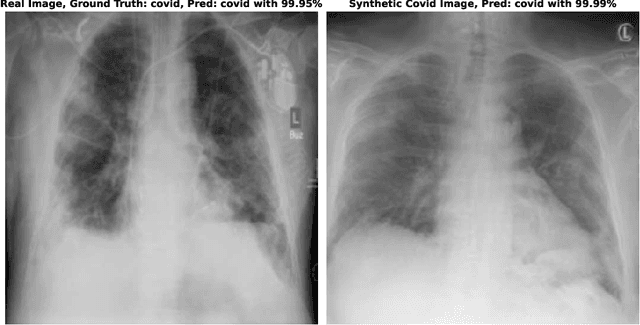

Since the beginning of the COVID-19 pandemic, researchers have developed deep learning models to classify COVID-19 induced pneumonia. As with many medical imaging tasks, the quality and quantity of the available data is often limited. In this work we train a deep learning model on publicly available COVID-19 image data and evaluate the model on local hospital chest X-ray data. The data has been reviewed and labeled by two radiologists to ensure a high quality estimation of the generalization capabilities of the model. Furthermore, we are using a Generative Adversarial Network to generate synthetic X-ray images based on this data. Our results show that using those synthetic images for data augmentation can improve the model's performance significantly. This can be a promising approach for many sparse data domains.